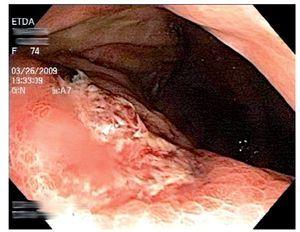

Mujer de 74 años de edad, residente del Distrito Federal, con antecedente de esclerodermia y cirrosis biliar primaria en tratamiento con ácido ursodeoxicólico. Inició ocho días previos a su ingreso con dolor abdominal epigástrico, náusea, distensión abdominal y melena. A la exploración física se encontró con signos vitales normales, mucosas pálidas, peristaltismo disminuido, sin otros hallazgos relevantes. Los exámenes de laboratorio mostraron hemoglobina 10.6 gr/dL, hematocrito 31%, leucocitos totales 8700 células/dL (4% de eosinófilos). Se le realizó endoscopia de tubo digestivo, que evidenció esofagitis erosiva grave, gastropatía eritematosa petequial, múltiples úlceras gástricas de 10 mm de diámetro con base de fibrina (Figura 1) y duodenitis erosiva (Figura 2). Se tomaron biopsias de los bordes de las ulceras y se envió en formol a estudio histopatológico que informó estrongiloidiasis gástrica, con inflamación crónica y aguda sin Helicobacter pylori (Figuras 3 y 4).

¿ Figura 1. Úlcera en cuerpo gástrico de 10 mm de diámetro con base de fibrina.